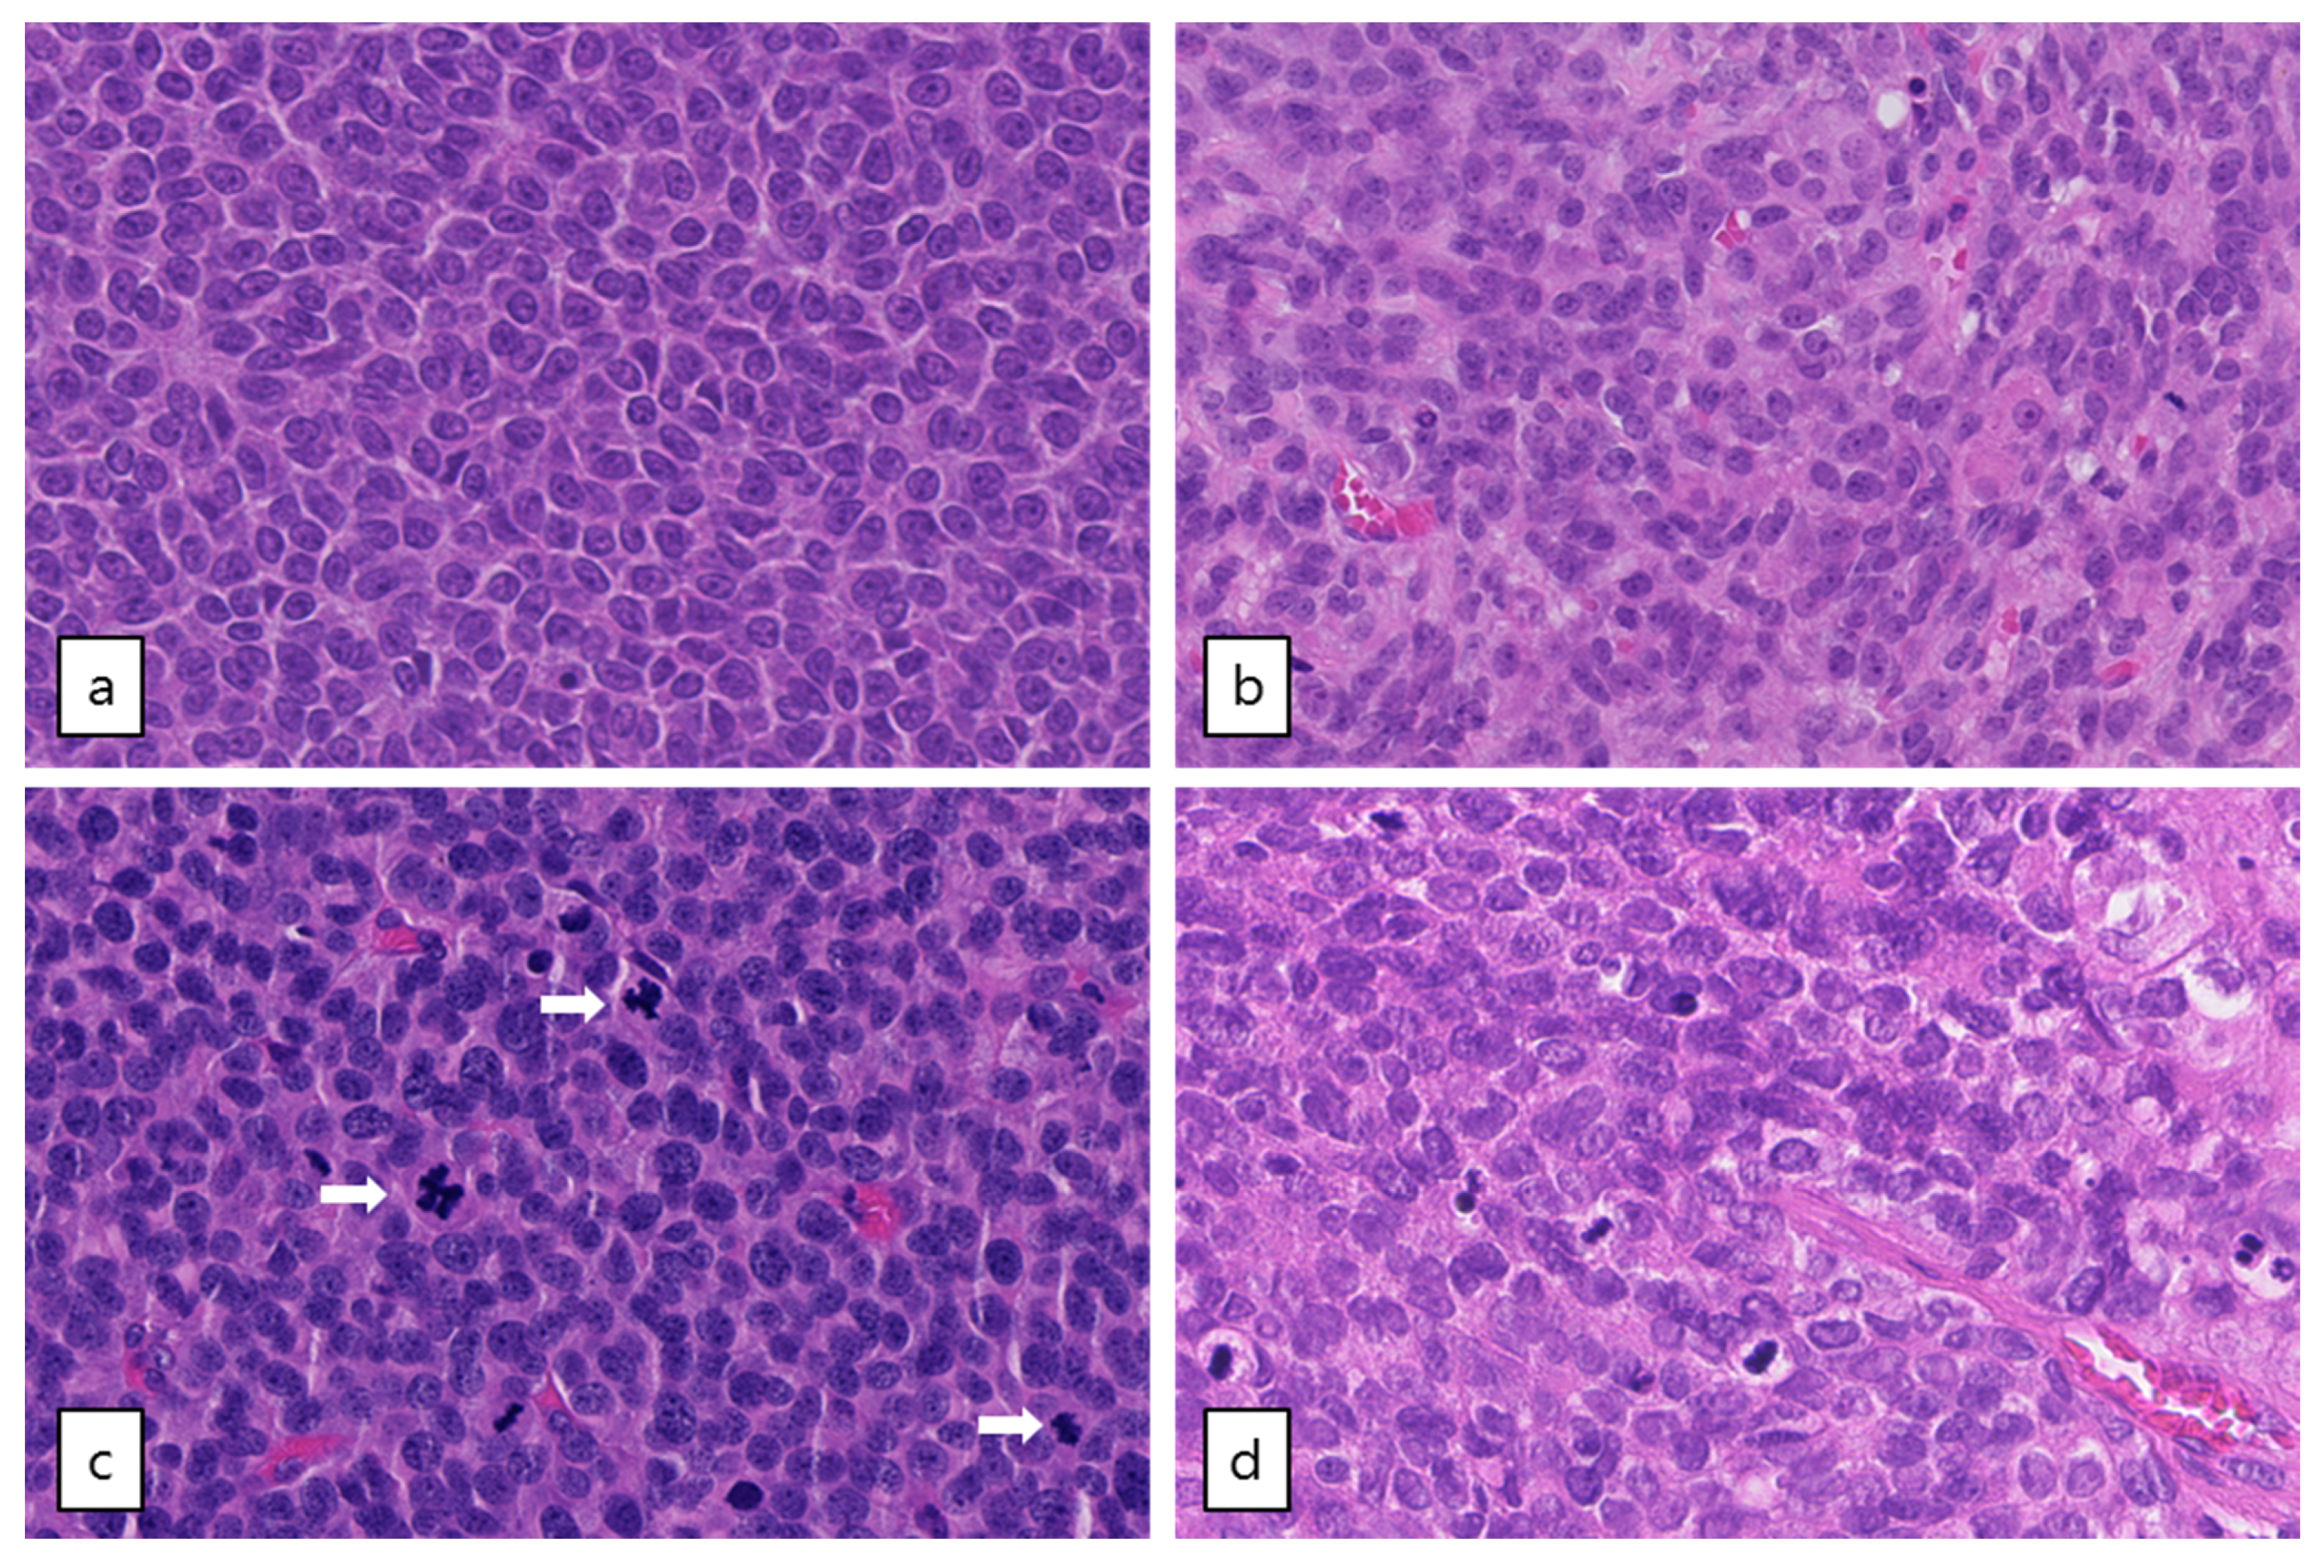

2.5. Subgroup of Patients with High-Grade AGCT Characterized by TP53 Mutation